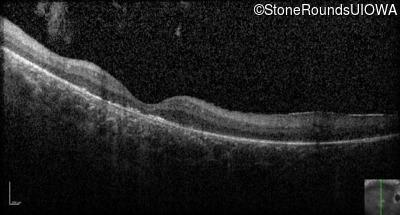

Optical Coherence Tomography - Right - Hand Motion sc

Exemplar / OCT Stack